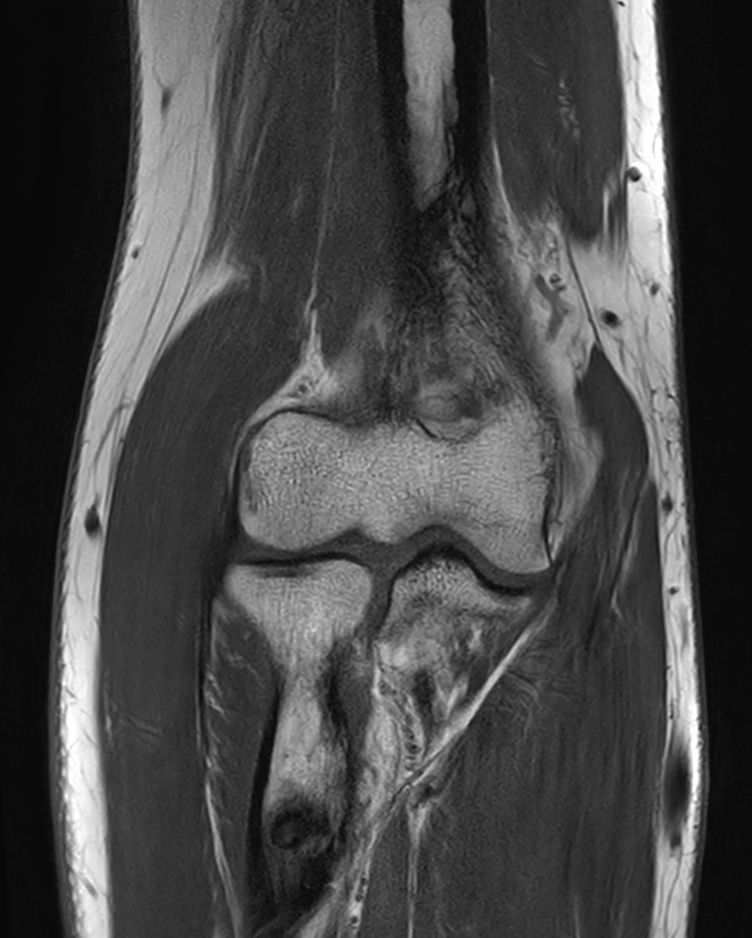

Routine Elbow

Routine imaging of the Elbow with the dS Small Extremity 8ch coil. MultiVane XD is used to deliver high resolution diagnostic images even in the case of patient motion. Compressed is used to speed up the entire exam with virtually equal image quality1.

PDw TSE FatSat Compressed SENSE